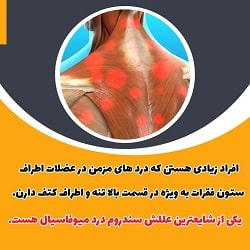

اگر به دنبال بهترین دکتر مغز و اعصاب بندرعباس هستید، باید به مهارت و تجربه پزشک در تشخیص و درمان مشکلات عصبی و مغزی توجه ویژهای داشته باشید. انتخاب یک متخصص با سابقه و دانش روز میتواند تأثیر زیادی در بهبود کیفیت زندگی شما داشته باشد. در بندرعباس، دکترهای مجرب زیادی وجود دارند که در زمینههایی مانند سردردهای مزمن، مشکلات نخاعی، تشنج، و اختلالات حافظه تخصص دارند. به عنوان مثال، دکتر الهام اوسپید یکی از پزشکان برجسته در این زمینه است که با ارائه خدمات دقیق و مؤثر توانسته است رضایت بیماران را جلب کند. برای یافتن بهترین دکتر مغز و اعصاب بندرعباس، توصیه میشود علاوه بر جستجو در اینترنت، نظرات بیماران قبلی و مشاوره با پزشکان عمومی را نیز در نظر بگیرید تا بتوانید تصمیم بهتری بگیرید و از درمانهای متناسب با وضعیت خود بهرهمند شوید.

8. چه علائمی نیاز به مراجعه به دکتر مغز و اعصاب دارد؟

علائم مانند سردردهای مزمن، تشنج، اختلالات حافظه، سرگیجه، دردهای شدید گردن و کمر، و مشکلات حرکتی نیاز به مشاوره و بررسی توسط دکتر مغز و اعصاب دارند.